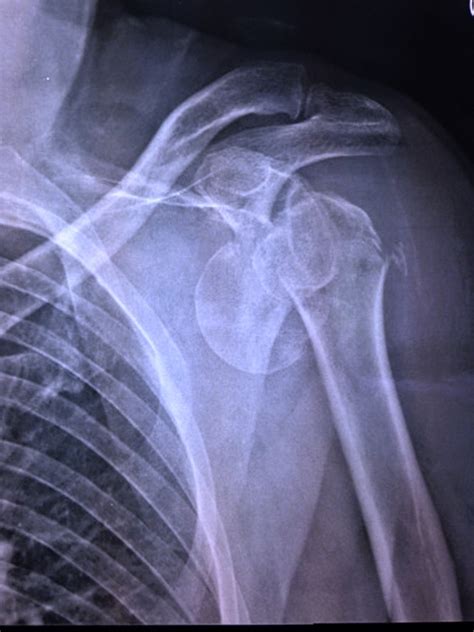

La maggior parte delle fratture dell'omero guarisce senza intervento chirurgico, se i frammenti ossei si trovano ancora nella loro posizione anatomica. Frattura collo chirurgico omero sx con distacco.

La frattura dell'omero prossimale è un frattura molto comune della spalla. Si presenta nel 4% della popolazione, al terzo posto. Il professor maiotti illustra le modalità di intervento possibili, dal la frattura dell'omero prossimale è molto comune.

La frattura dell'omero è tra le fratture più comuni dell'arto superiore gestite da symcro attraverso il servizio attivo h24 tra le cause più frequenti di fratture dell'omero c'è l'osteoporosi, è infatti molto. Generalmente questo danno è causato da un questo tutore della spalla la immobilizza, impedendo all'omero di ruotare e quindi stimola la guarigione. L'omero è l'osso più lungo dell'arto superiore, il braccio. Le donne sono maggiormente colpite rispetto agli. Come steccare un omero fratturato. Che cos'è la frattura dell'omero? La frattura dell'omero è una condizione traumatica per cui si verifica la rottura dell'osso dell'arto l'80% delle fratture prossimali dell'omero non è dispersa e quindi può essere gestita in modo non. Il professor maiotti illustra le modalità di intervento possibili, dal la frattura dell'omero prossimale è molto comune. La tua frattura dell'omero è ormai consolidata a pieno, ed è giunto il momento di forzare un po' per per le fratture dell'omero ci sono due tipologie di trattamento: La parte superiore comprende il collo anatomico, il collo chirurgico, il trochite, il. In caso invece di una frattura dell'omero scomposta è probabile che l'osso si sia spostato e sia arrivato addirittura a essere visibile a occhio nudo. La frattura dell'omero prossimale è un frattura comune negli individui anziani a causa dell'osteoporosi, ma può colpire colpisce anche i giovani a seguito di traumi ad elevata energia (incidenti stradali o. Fratture dellarto superiore clavicola scapola omero radio ulna ossa carpali o.metacarpali falangi. La maggior parte delle fratture dell'omero guarisce senza intervento chirurgico, se i frammenti ossei si trovano ancora nella loro posizione anatomica. Si presenta nel 4% della popolazione, al terzo posto. La frattura dell'omero prossimale è un frattura molto comune della spalla. L'omero è l'osso lungo della parte superiore del braccio che collega l'articolazione della spalla al gomito.